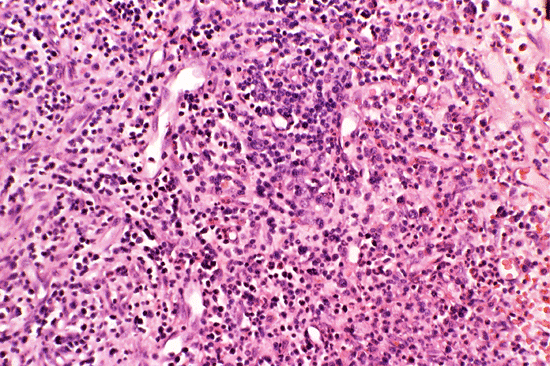

A bone marrow biopsy was performed. The followings are representative photos taken from the bone marrow biopsy:

Com401-1-B1.gif (137270 bytes) Com401-1-B2.gif (127871 bytes) Com401-1-B3.gif (174580 bytes) Com401-1-B4.gif (156845 bytes) Com401-1-B5.gif (138860 bytes)